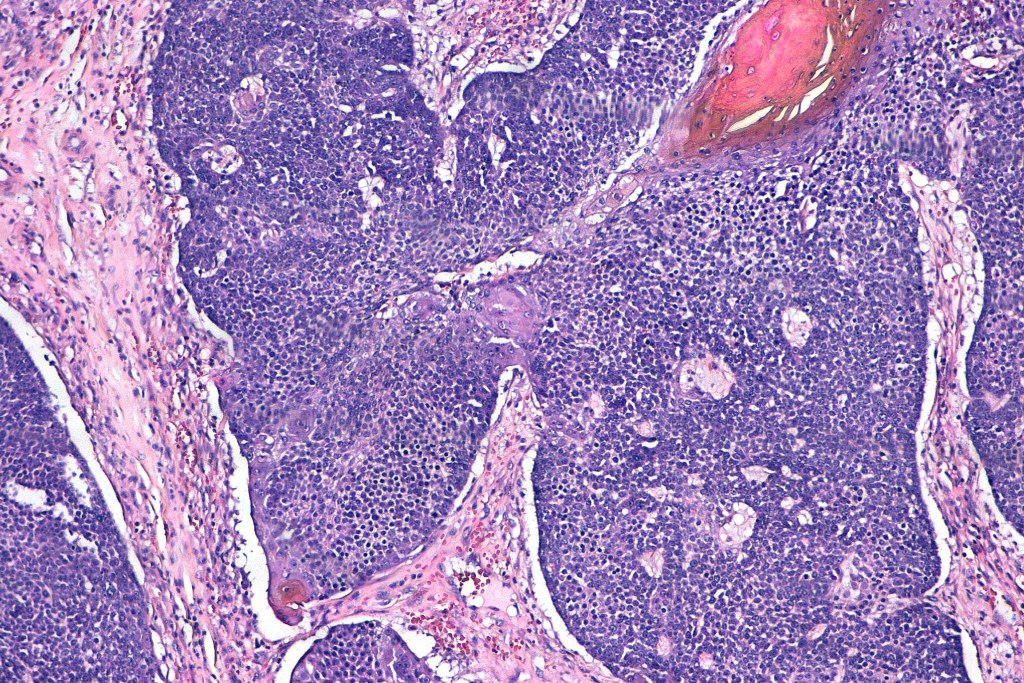

•Multilobulated tumor in dermis +/- subcutaneous fat with a fibrous pseudocapsule

•Basophilic small cells which transition towards supramatricial (orange staining) and ultimately ghost cells with intensely eosinophilic cytoplasm

•Intense mitotic activity may be seen in early lesions (this should not be interpreted as implying malignant potential)

•Foreign body reaction